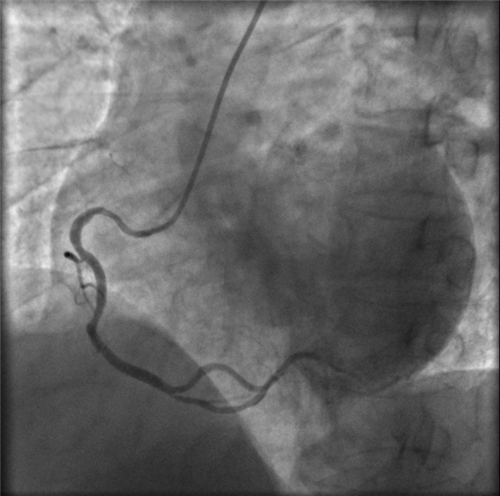

右冠近段嚴(yán)重狹窄,未見右向左的側(cè)枝循環(huán)

再行右冠造影,右冠近段也嚴(yán)重狹窄,未見右冠向左冠的側(cè)枝循環(huán)。